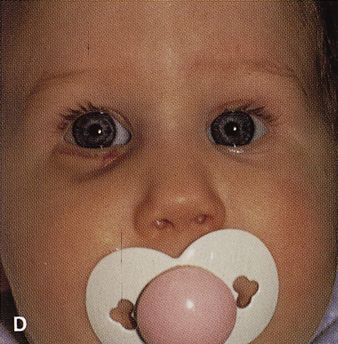

Fig. 14. A,B. Large intraorbital lymphangioma causing proptosis and optic nerve compression

in a 2-year-old child. C. View of the left orbit from above after removal of the frontal bone flap, including

the supraorbital rim and orbital roof. An extensive exposure

of the entire superior and lateral orbit is afforded. The levator

and superior rectus complex is being retracted laterally with a muscle

hook, whereas the Freer elevator retracts the superior oblique muscle

medially. The frontal nerve can be seen running from posterior to anterior

over the superior orbit. The orbital mass is exposed in this fashion. D. The fronto-orbital bone flap is wired back in place after completion of

the procedure. E. Postoperative appearance of the patient. F. The postoperative CT scan shows complete removal of the lymphangioma. This

large and diffuse lesion would have been difficult to remove with